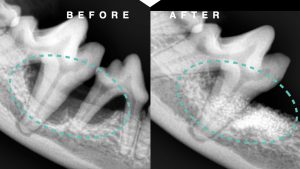

全身麻酔下での精査を行い、歯科レントゲン検査にて歯槽骨の融解を認め、スケーリングを行い切歯を抜歯しました。

また、隣接する犬歯の根本まで歯石が沈着していたため、歯肉を切開し歯根部までスケーリングを行い縫合しました。